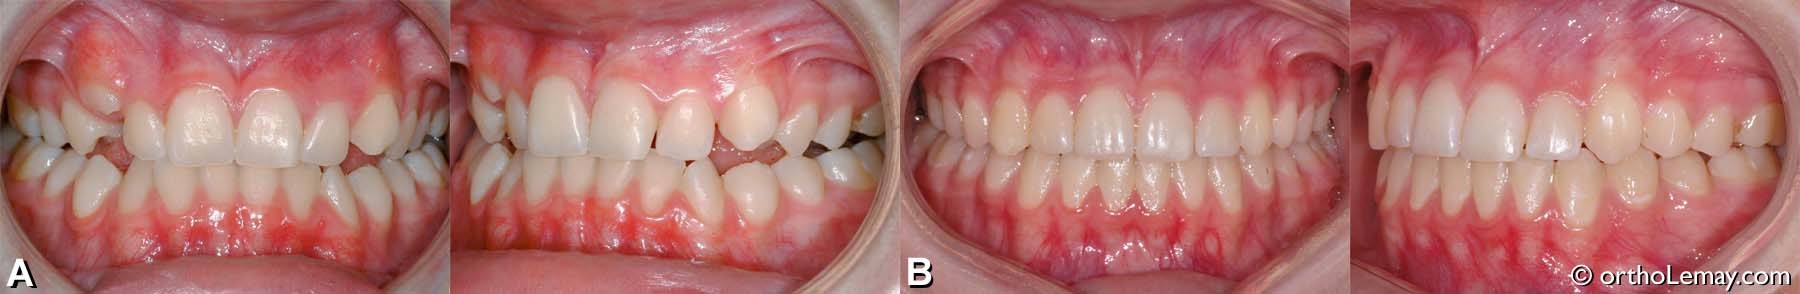

Exemple de traitement de malocclusion classe 1 (17)

(A) Adolescente de 14 ans avec surplomb antérieur vertical et horizontal excessifs (overbite et overjet) et manque d’espace, surtout à l’arcade inférieure.

(B) après les corrections, les surplombs ont été régularisés ce qui améliore la fonction et l’esthétique.